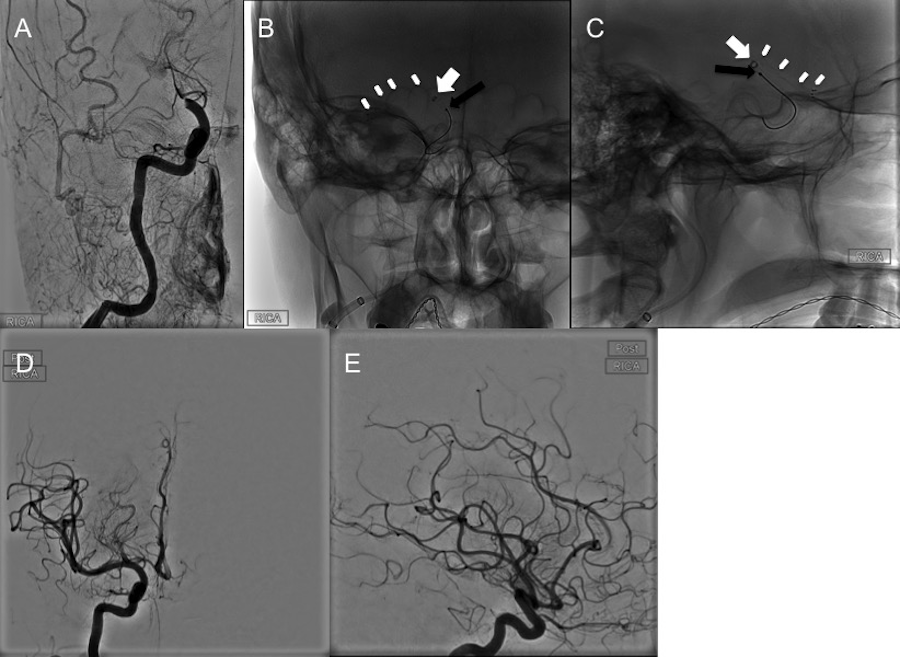

Case 1

A 50-year-old male, modified Rankin scale (mRS) 0, presented with the acute onset of aphasia, right-sided facial droop, and right hemiplegia, with a National Institute of Health Stroke Scale (NIHSS) of 23. A computed tomography angiography (CTA) of the head and neck demonstrated a left cervical ICA dissection and an intracranial carotid “T” type of occlusion. A CT perfusion (CTP) indicated a large mismatch between the small core (infarct) and the penumbra (viable tissue at risk). The patient was not a candidate for the recombinant tissue plasminogen activator (rtPA), as the time of his stroke/symptom onset was unknown. He was thus referred to our service for endovascular treatment of his anterior circulation ELVO. The procedure was carried out under general anesthesia since the patient was agitated. In anticipation of the potential need for emergency extracranial carotid artery stenting, the patient was loaded with 600 mg of aspirin through an orogastric tube. Once the diagnostic angiogram had confirmed an occlusive dissection of the left cervical ICA, a Precise Pro RX 7x40 mm stent (Cordis, Miami, FL) was placed. Reestablishment of antegrade flow through the cervical left ICA then demonstrated an occlusion of the ipsilateral supraclinoid ICA just distal to the takeoff of the ophthalmic artery and extending up to the distal left M1 (Figures 1A-1B). As described in a recently proposed scheme to classify the tortuosity of the ICA, the cavernous carotid artery of this patient was a type IB (mild tortuosity) with open configuration/angles of the anterior and posterior genu, with the subcategory determined by the posterior genu angle, which, in his case, was equal to 90 degrees [10]. For this particular case, we used an 8 Fr FlowGate (Stryker Neurovascular, Fremont, CA) BGC positioned distal to the recently placed carotid stent, the Arc™ support catheter (Medtronic, Irvine, CA) as the intracranial intermediate AC, and a Marksman™ microcatheter (eV3, Irvine, CA), which was navigated over a Synchro-2 microwire (Stryker Neurovascular, Fremont, CA)  beyond the occluded left M1. For the first thrombectomy pass, a Trevo® XP ProVue 6 x 25 mm Retriever (Stryker Neurovascular, Fremont, CA) was deployed spanning from the distal left M1 segment down to the distal supraclinoid ICA. After the first thrombectomy pass, follow-up DSA runs demonstrated persistent occlusion of the most distal supraclinoid left ICA and ipsilateral M1 segment. A second thrombectomy pass was then performed, with the stent retriever spanning a proximal M2 branch down to the proximal M1 segment (Figures 1C-1D). Follow-up DSA runs showed recanalization of the left supraclinoid ICA and left M1. There was also complete patency of the left anterior cerebral artery (ACA). However, there was residual occlusion of the superior left M2 branch. A third thrombectomy pass was performed using a similar technique, this time with the Trevo® Pro 18 microcatheter (Stryker Neurovascular, Fremont, CA). The Trevo® Pro 18 microcatheter was then navigated slightly more distally, this time into the proximal superior division of the left M2 branch. A Trevo® XP ProVue 4 x 20 mm (Stryker Neurovascular, Fremont, CA) stent-retriever was then delivered across the occluded segment. Follow-up angiograms demonstrated complete patency of the left supraclinoid ICA, ACA, M1, and M2 branches. As the left M1 was recanalized, residual occlusion of the left anterior temporal artery was noted. Using a Trevo® XP ProVue 3 x 30 mm stent-retriever (Stryker Neurovascular, Fremont, CA), two additional thrombectomy passes of the left anterior temporal artery occlusion were performed. In each of these thrombectomy attempts, the Arc™ catheter was again navigated against the proximal aspect of the clot, this time, situated near the ostium of the left anterior temporal artery. It is unclear why recanalization of the left anterior temporal artery was unsuccessful. No further recanalization attempts were made as some retrograde filling of the vessel territory via leptomeningeal collaterals existed. Final DSA runs demonstrated thrombolysis in cerebral infarction (TICI) 2B flow through the left anterior cerebral circulation, with a cutoff of the left anterior temporal artery (Figure 1E). The procedure was then concluded, and the patient was extubated and transferred to the neurointensive care unit. By postoperative day (POD) 2, the patient had made significant improvement with an NIHSS of 8, with some mixed aphasia, and 4/5 strength in his right hemibody. At POD 30, the patient had only mild dysarthria and some word finding difficulty, near-normal motor strength, and had been discharged from physical therapy and occupational therapy but was still undergoing speech therapy.